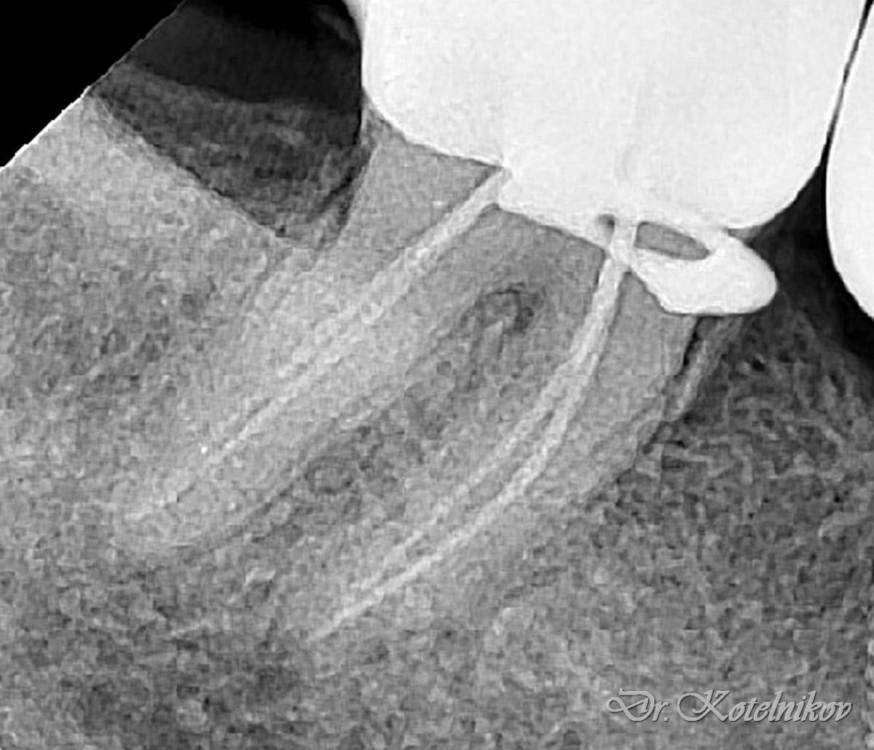

Ico Опубликовано 7 октября, 2022 Автор Поделиться Опубликовано 7 октября, 2022 В первом кейсе все стандартно,просто не каждый день такие антенны попадаются.Во втором 3 изгиба,но их хорошо в ручном режиме берут патфайлы, апексы все соединяются в нижней трети.Третий случай - ретрит со ступенькой был,тут пре рейс 30.06,тоже патфайлы + профайлы 02 конуса,далее шейпинг S1.На четвертом снимке телега не моя,направили помочь.За 1ч15м удалось извлечь фрагмент ,сначала байпас,потом чаком снял кривизну немного,и рядом нарезал площадку,которая позволила озвучить фрагмент сбоку,фрагмент выплыл стандартно. 2 1 2 Ссылка на комментарий